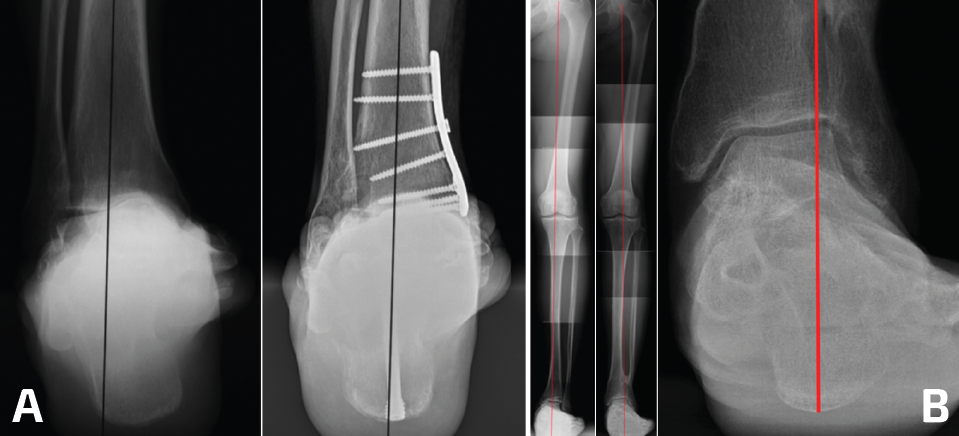

- Alinear el centro de rotación del tobillo (proceso lateral del talo como referencia) bajo el eje anatómico de la tibia (Figura 4B)(7).

Figura 4. A: proyección de Saltzman; B: telemetría.

El estudio radiológico se realiza siempre con radiografías en carga de tobillo y pie bilateral anteroposterior, oblicua y lateral. El estudio en la actualidad se complementa con la evaluación de la alineación del retropié mediante la proyección de Saltzman (Figura 4A), además del uso de una telemetría de las extremidades inferiores, en la que idealmente se logre visualizar el calcáneo para poder determinar el verdadero punto de apoyo del eje mecánico cadera-calcáneo, que se ha propuesto como la mejor manera de planificar el manejo de la artrosis asimétrica de tobillo que involucre cirugía de realineamiento (OTT-SM/OTT de calcáneo) (Figura 4B)(14).

En las radiografías simples con carga se evalúan las deformidades en los planos coronal y sagital. Las mediciones en el plano coronal son la superficie articular tibial distal (TAS-LDTA) con valores normales de 91 a 93° y el ángulo tibiotalar (TTA) con valores normales de 91,5 ± 1,2°. La inclinación talar (talar tilt) se calcula entre la diferencia de la TAS y el TTA. Se considera que un talar tilt con relevancia clínica es aquel mayor de 4°, considerando este valor como límite máximo de normalidad(6,15). La medición en el plano sagital es el ángulo tibial lateral o ángulo tibial anterior distal (TLS-ADTA), con valores normales de 81 ± 5°. En la clasificación de las malalineaciones con OA asimétricas de tobillo se hace más énfasis en la necesidad de corroborar que el centro de rotación del talo (considerado en el centro del proceso lateral del talo) esté en línea con el eje anatómico de la tibia en la radiografía lateral(7,8)(Figura 5).